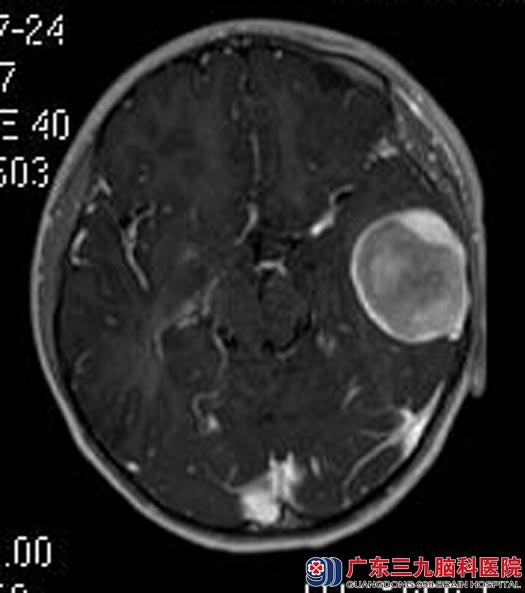

鲁明主任建议行手术治疗,经家人同意后,在全麻下行左侧颞部中颅窝底占位切除术,术中显微镜下见中颅窝底白色肿瘤组织,质硬、血供丰富,边界清晰,肿瘤基底位于颅底硬膜,沿颅底硬膜向下切断肿瘤基底并止血,再沿肿瘤周边分离分块全切肿瘤,手术顺利。术后豆豆食欲明显好转,已康复出院。术后病理结果:神经纤维瘤。

手术前